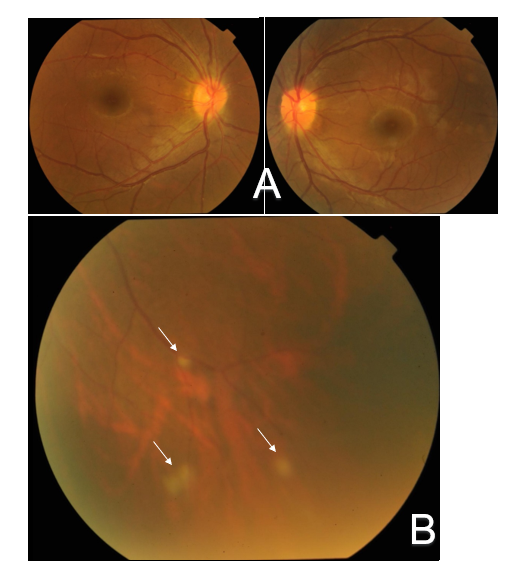

An 18-year-old Chinese girl presented at our hospital with sore eyes, photophobia and blurred vision. Ocular preliminary examinations in our department revealed best-corrected visual acuity (BCVA) of 20/20 in the patient's both eyes. Anterior segment findings only included mild conjunctival hyperemia, mutton-fat keratic precipitates and slight aqueous flare in the anterior chamber in her both eyes (Figure 1), while fundus examinations revealed only optic disc hyperemia in both eyes and focal punctate retinal infiltrations in the inferior peripheral retina of the left eye (Figure 2) After a detailed medical history inquiry, we knew that she had been suffered from recurrent ankle and wrists swelling since she was 3 years old without any family history. Skin manifestations were not apparent except only roughness located on the trunk and forearms. Her past blood examinations showed only an elevated C-reactive protein level of more than 20 mg/dL (normal: less than 0.2 mg/dL). Between the ages of 3 and 6, the patient just had two fevers, each accompanied by joints swelling and pain involving wrists, right ankle and proximal interphalangeal (PIP) joints of feet. Methotrexate and prednisolone have been tried, and prednisolone was the most effective for her, so she has been taking it till now, at a dose of 5 mg daily at present.

Figure 2: Fundus photographs show optic disc hyperemia in both eyes (A) and significant focal punctate infiltrations (arrows) in the inferior peripheral retina of the left eye (B).